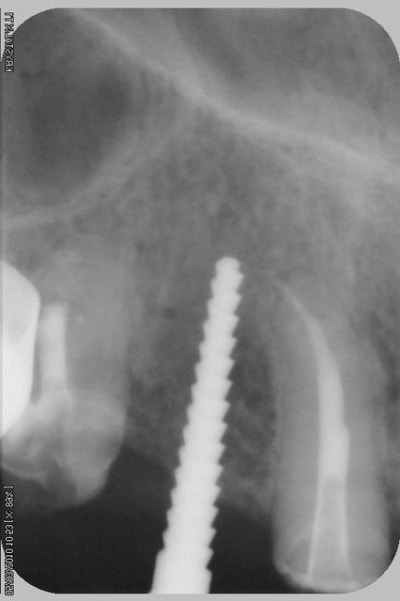

tiens...un ptit cas...

dans ce petit cas...j'ai commencé avec le kit MIS...et fini ma voie crestale avec le kit HBS...

ok, c'est un mini soulevé...mais bon , c'est un exemple...

juste une précision...premier foret 1.3mm sur 8mm...expansion pour mettre un implant de 4x10...

j'ai juste "léché" la préparation du site final avec le foret terminal du système...sur 8mm...avant d'insérer l'implant...stab primaire au top...blocage à 40 Ncm...

rien...une cloison du sinus...;-))

???? tu as un pano ou un scan je ne situe pas ça comme une cloison, mais je vois mal.

j'ai la pano au cab...pas de problème...çà peut aussi être un épaississement de la membrane dans ce cloisonnement...il a eu un bon rhume quelques semaines avant...